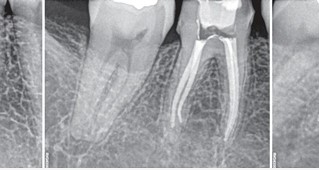

Emotion Icon신경치료에 성공율을 좌우하는것은?

신경치료후에도 잔존세균과 어떠한 자극원이 근단부로

방출되어 생기는 염증을 의미합니다.

근관치료의 성공은 근관 내우와 외부의 연결 경로를

밀폐하는 것에 달려 있고, 이를 위해 본원에서는 MTA충전재로

밀폐환경을 더 완벽히 조성하여

실패율을 줄이는데 집중하고 있습니다.